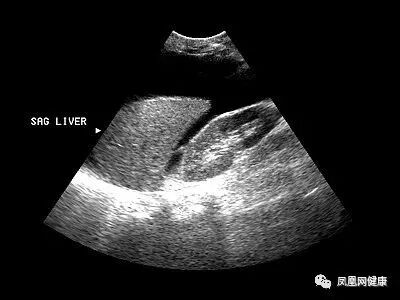

虽然乙肝病毒多数可以控制,但难以彻底清除,慢性乙肝感染是肝癌的主要危险因素,因此定期监测必不可少。有乙肝、肝硬化、肝癌家族史等高危因素者至少每年查一次甲胎蛋白、肝脏超声、肝功能,必要可行时磁共振检查。

专家提醒,肝病发病初期症状往往不典型,因此患者常常延误了治疗时机。体检是及时发现肝脏疾病的有效手段,专家建议,普通人应每年进行一次肝脏检查。

尤其是乙肝病毒携带者、肝硬化患者、长期酗酒人士、甲胎蛋白轻度升高人士,属于肝癌的高危人群,即使没有不适症状,每年最少体检两次,最好每三个月体检一次。

那么,体检查什么?

肝B超检查+甲胎蛋白。